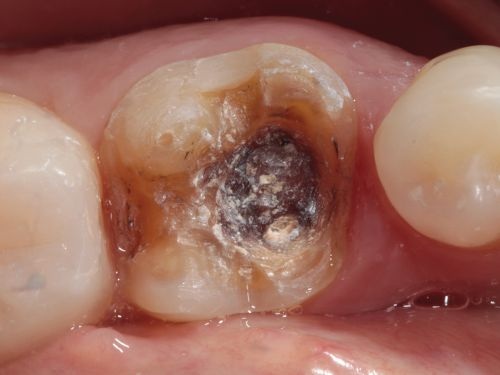

A 50-year-old female patient presented for the replacement of an inadequate restoration on the mandibular left first molar. Following removal of the existing restoration, the decision was made to proceed with the indirect composite restorative technique because of the extent of the necessary preparation (Fig. 9).

Initially, selective enamel etching was performed, followed by the application of a universal adhesive. Subsequently, deep margin elevation and filling of retentive areas were carried out using a flowable composite resin (Voco’s GrandioSO Heavy Flow, shade A3). The objective of this step was to elevate the cervical margin to a supragingival position. The entire remaining tooth structure was covered with GrandioSO Heavy Flow, resulting in a smooth and expulsive surface conducive to the indirect procedure. Final refinement of the preparation was performed with a fine-grit diamond bur to smooth the margins (Fig. 10).